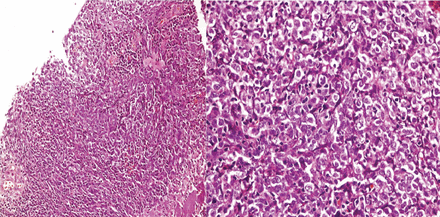

病理组织检查质量符合一个未分化的鳞状细胞鼻咽癌(NPC) (图3)。中腔剂量的放疗30 Gy 15分数每周的开始,和化疗计划。自从开始治疗,病人所指出的一些改善复视和上睑下垂。他的头痛持续下去,虽然强度显著降低。